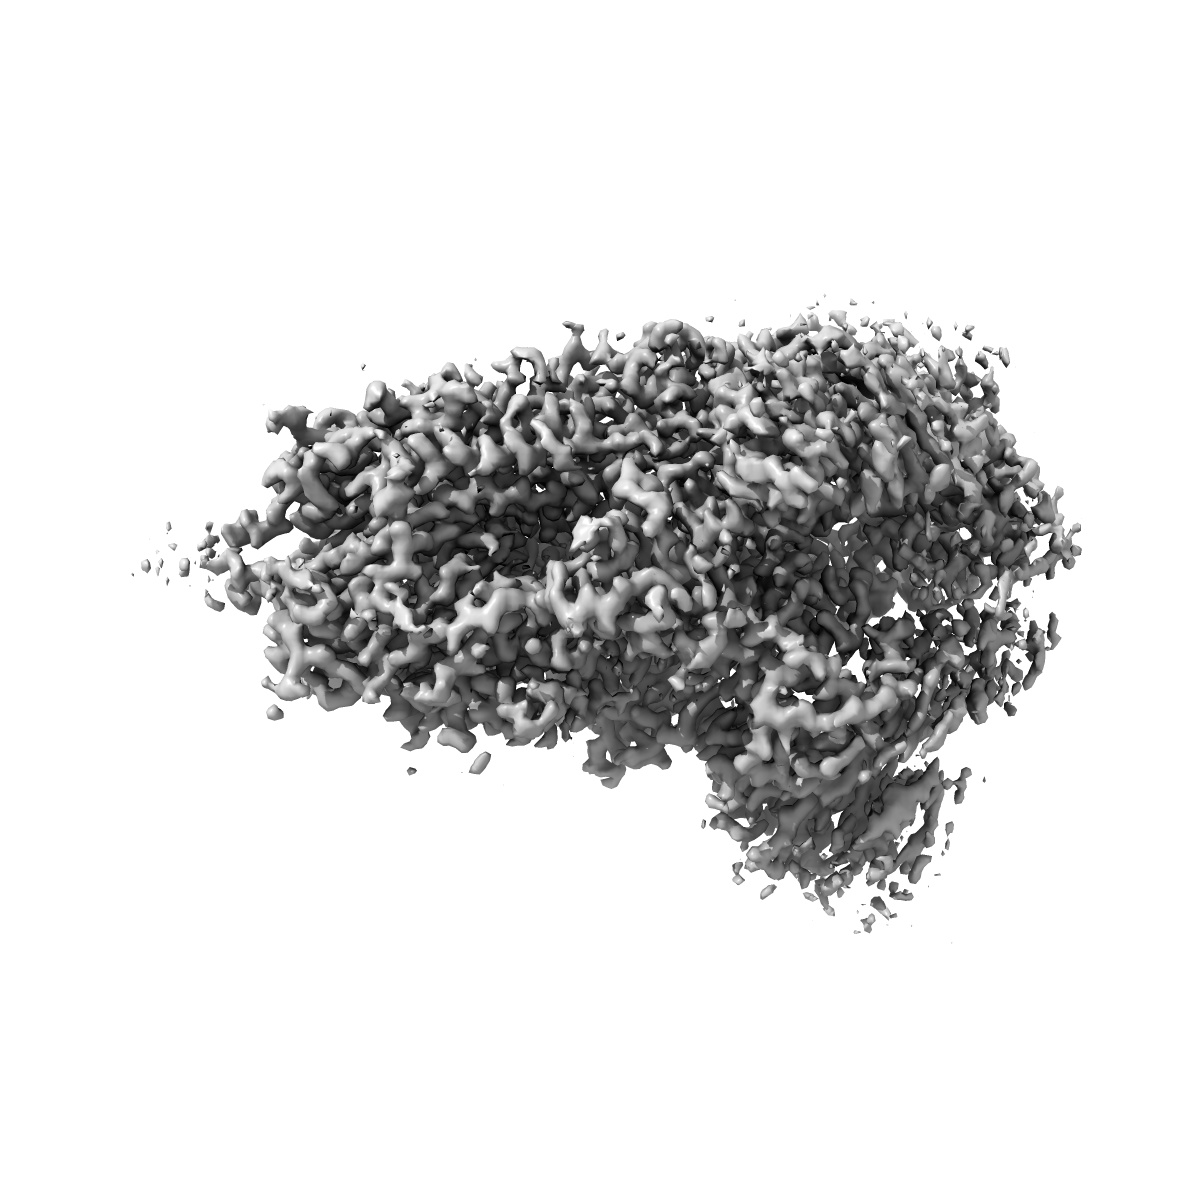

Down-state locked rS2d SARS-CoV-2 spike ectodomain in the RBD-down conformation, State 1

Single-particle3.13 Å

Fitted models: 7tla